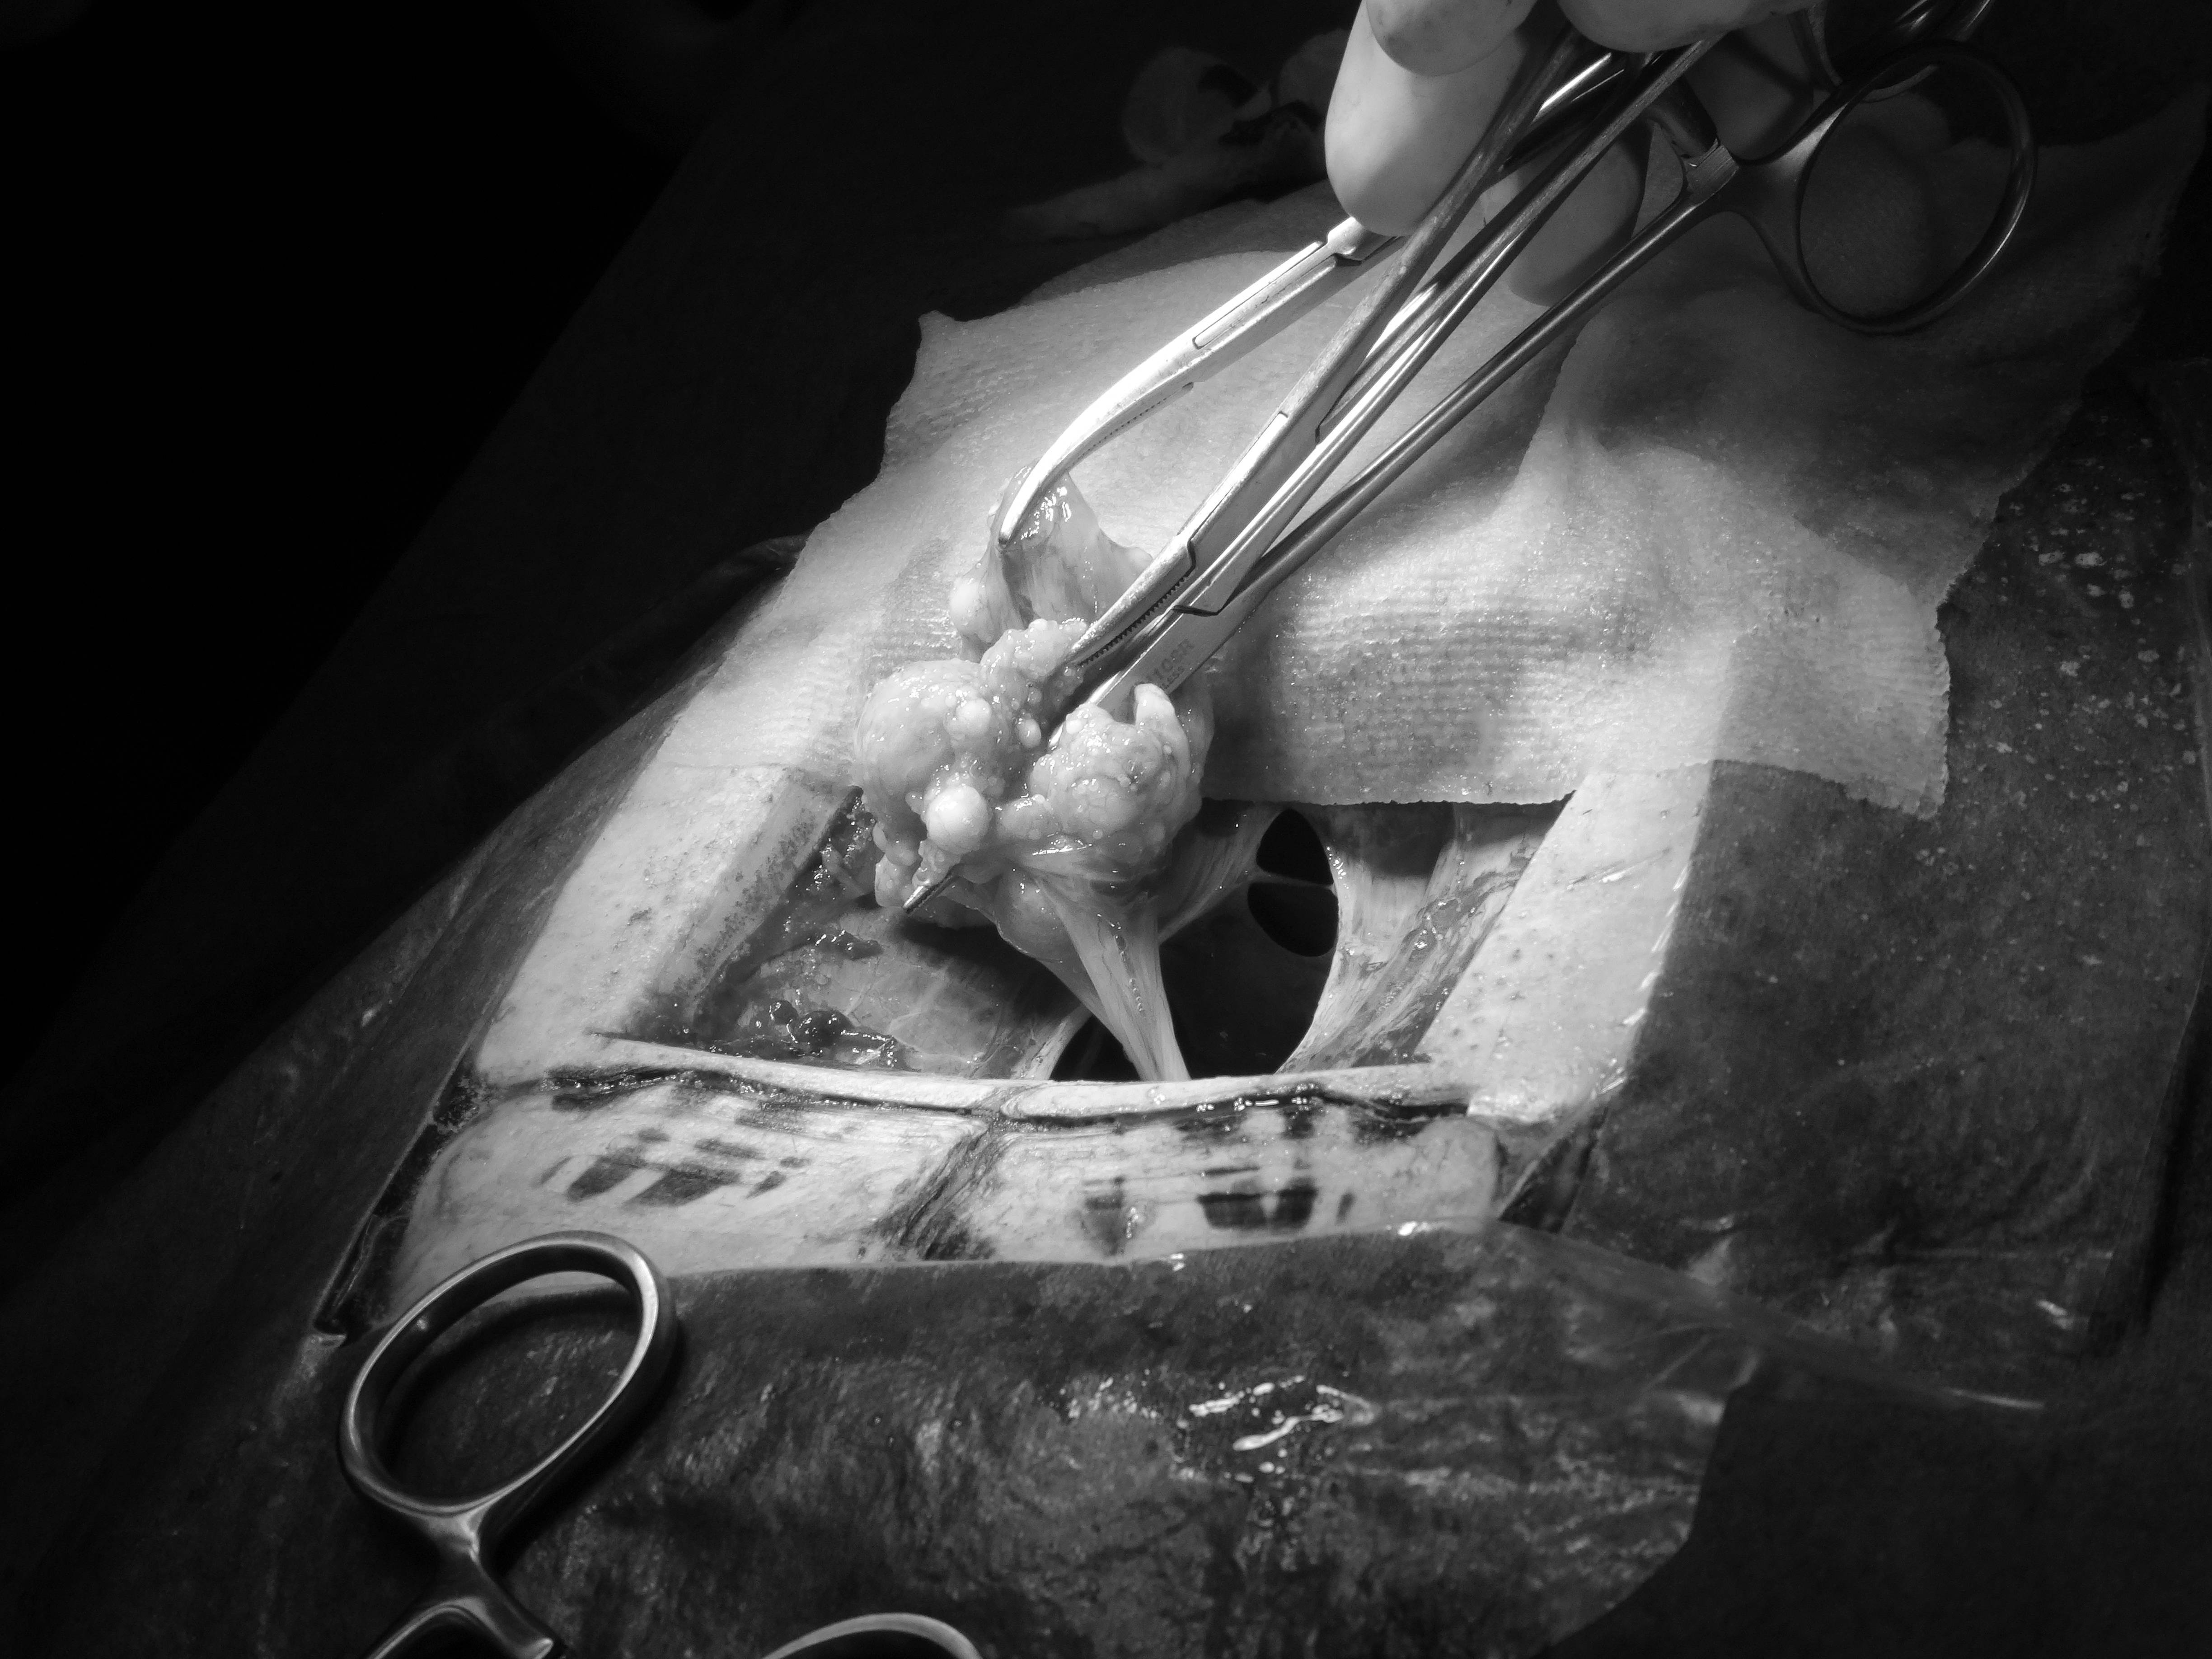

そのあとは哺乳類や鳥類と同じように、腹膜を切開して、卵巣と卵管を切除しました。

なかなか産まれなかった卵は、卵管の外にある状態(卵墜といいます)だったので、取り出しました。

一部は膀胱にくっついていたので、その部分の膀胱を切除し縫合しました。